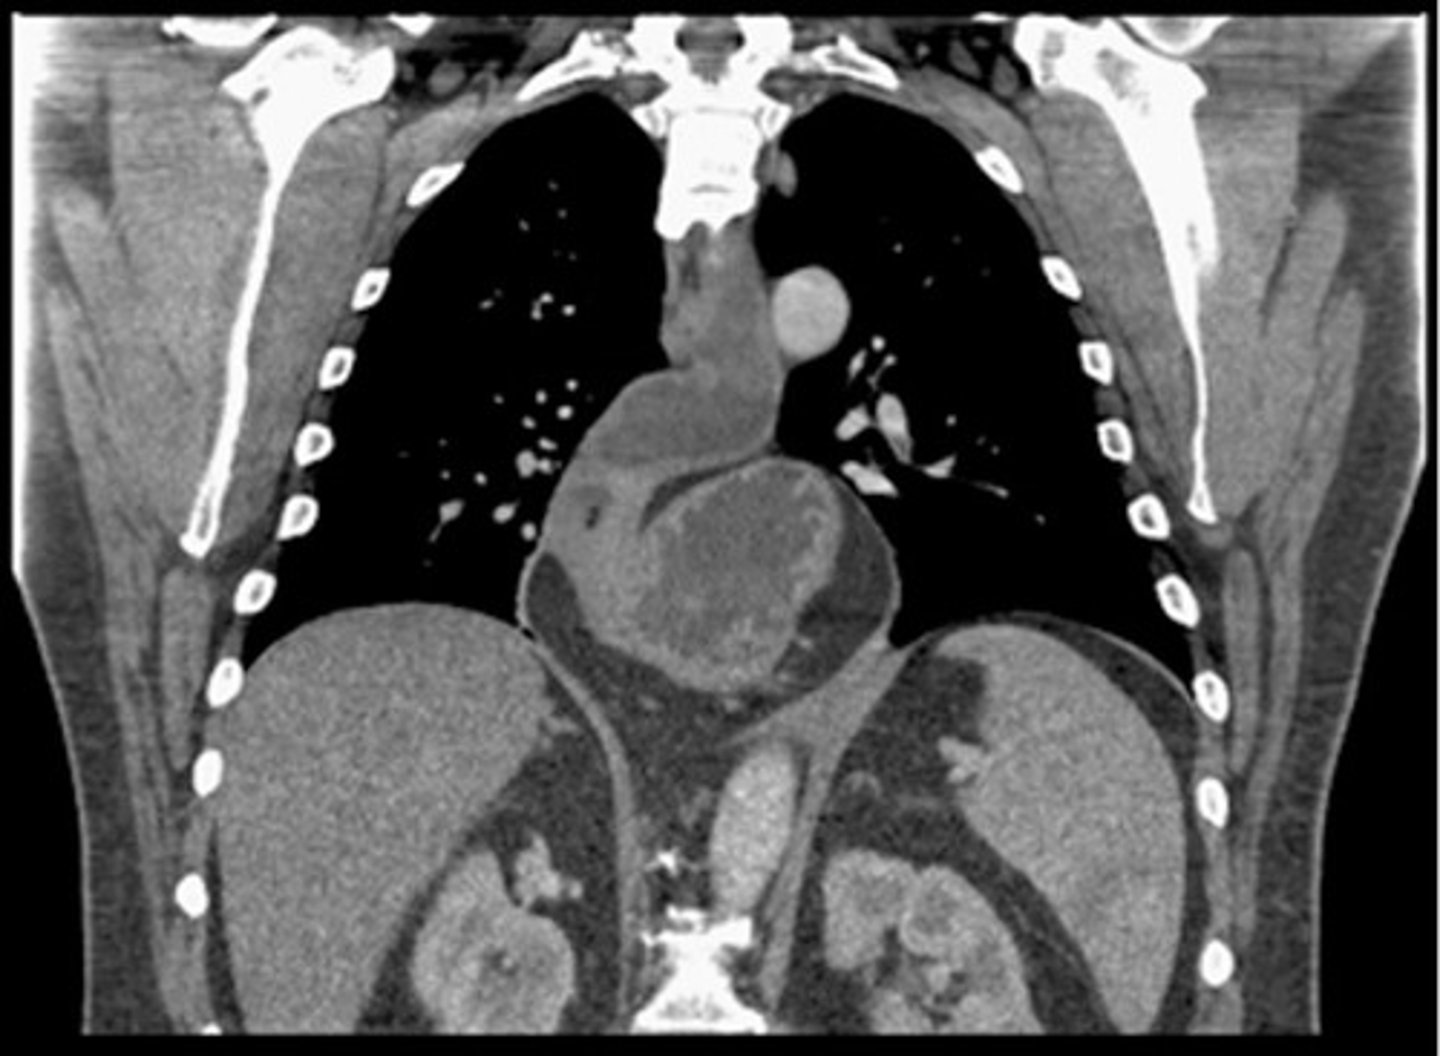

Paraesophageal hernia CT

Paraesophageal hernia CT (pic 2)